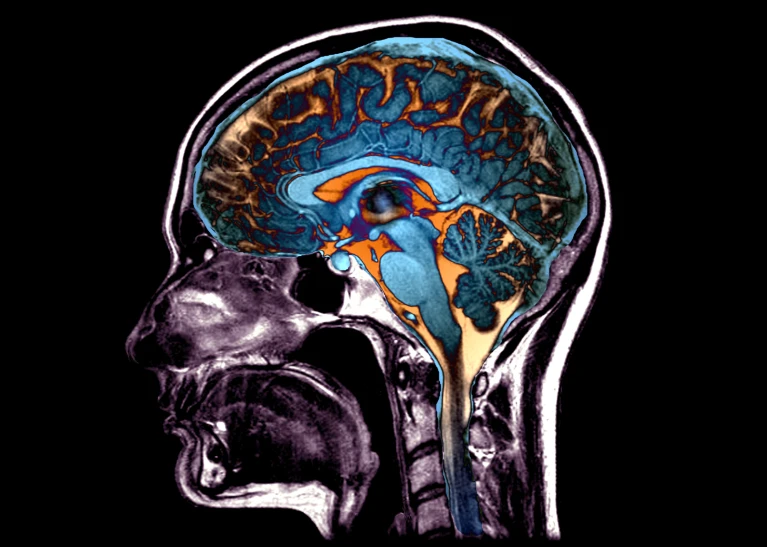

Recientemente, un equipo de científicos liderado por Christos Davatzikos, de la Universidad de Pensilvania (EE UU), ha publicado en Nature Medicine un trabajo en el que se han identificado diferentes formas en que nuestro cerebro se desmorona con el paso de los años y que promete una medida más individualizada del envejecimiento. Analizaron 50.000 escáneres cerebrales que revelaron cinco formas distintas de atrofia cerebral asociada al envejecimiento y a la aparición de enfermedades neurodegenerativas. Aunque el ojo humano no puede detectar los cambios sutiles que existen entre estos cinco patrones, lograron identificarlos utilizando tecnología de aprendizaje automático. Los autores entrenaron un algoritmo mostrándole escáneres de 1.150 personas sanas de entre 20 y 50 años y de casi 9.000 personas a partir de esa edad, sanas y con deterioro cognitivo.